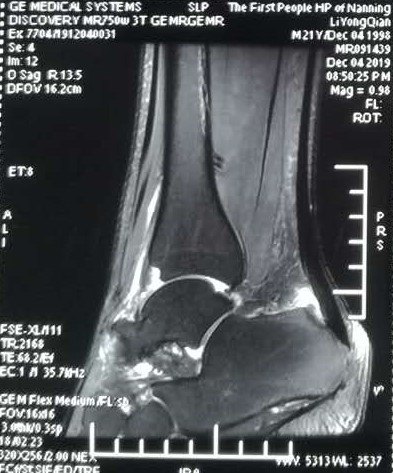

mri可现实跟腱腱鞘周围肿胀,退行性变和跟腱大片撕裂.